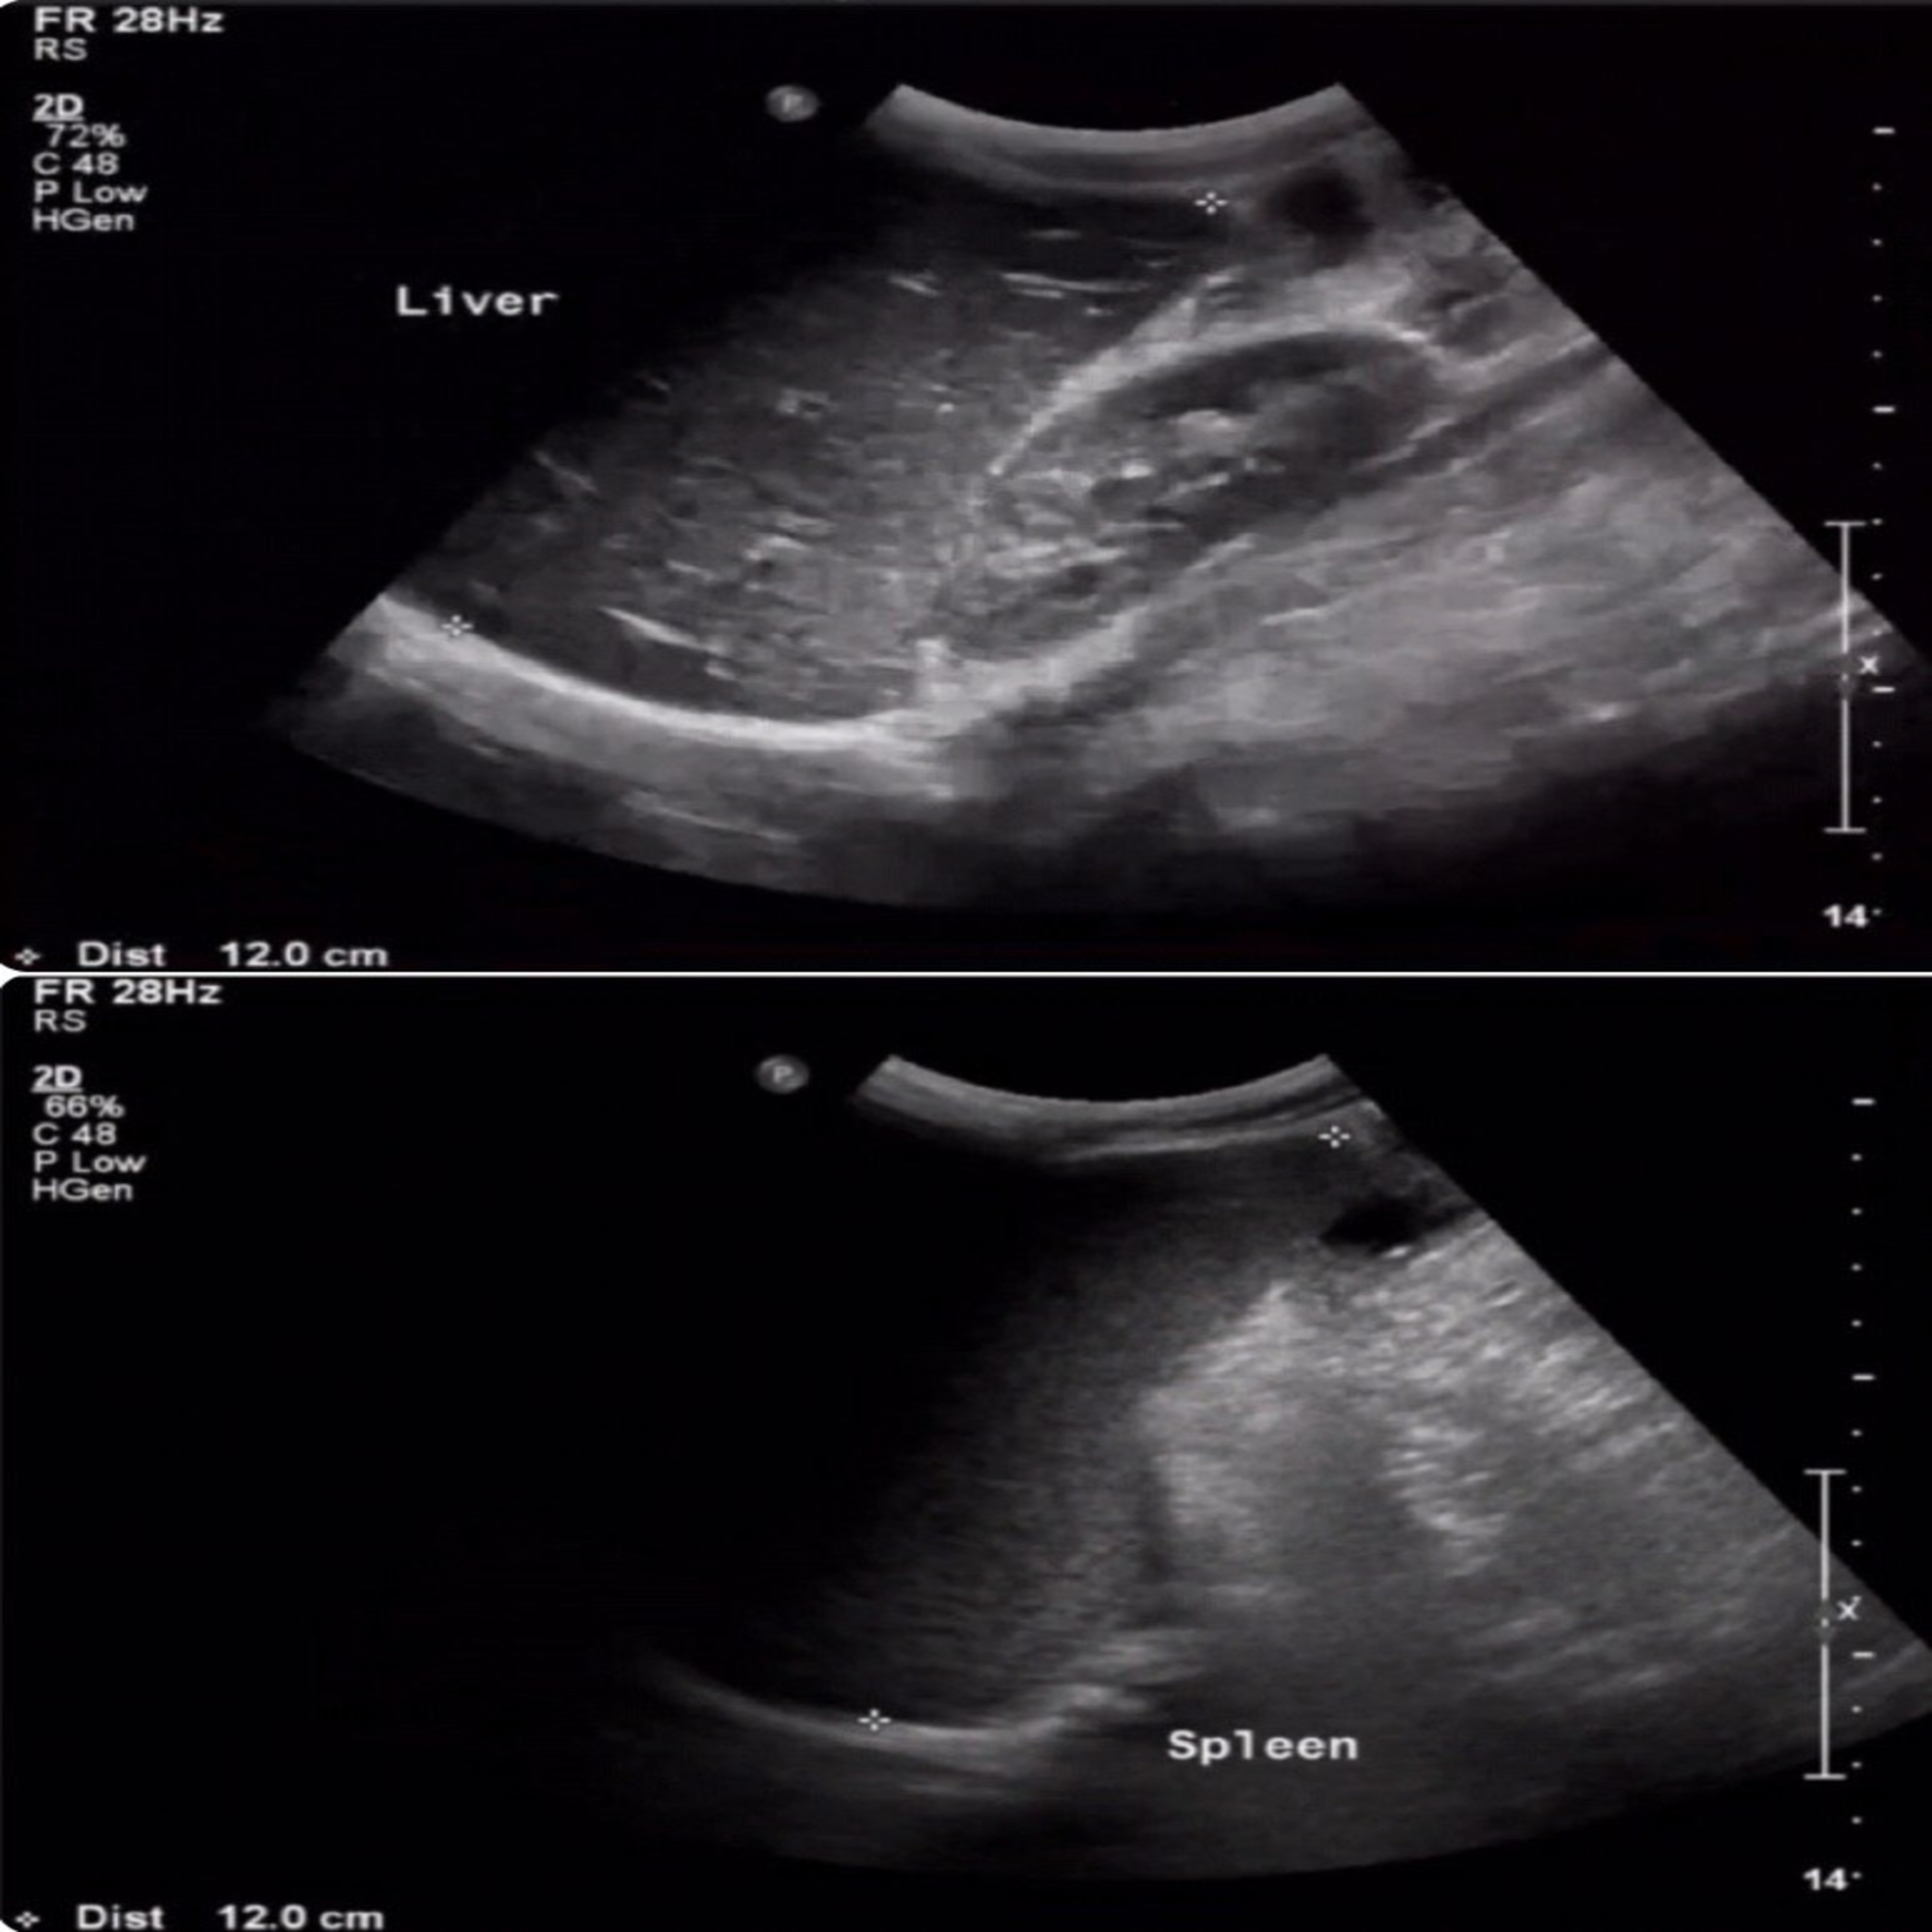

The initial laboratory findings showed leukopenia, lymphopenia, and thrombocytopenia with a white blood cell count of 3.0 x 109/L, lymphocyte count of 1.00 x 109/L, and platelets count of 90 x 109/L. His neutrophil count (2.72 x 109/L) and hemoglobin level (13.4 gm/L) were within reference ranges. His C-reactive protein was elevated (92.1 mg/L). He had mildly elevated aspartate transaminase level (90 U/L), and his alanine aminotransferase level was within the reference range (33 U/L). His initial serum electrolyte levels were within reference range apart from mild hyponatremia (130 mmol/L). His peripheral blood smear was negative for blast cells, and it showed a low platelet count (with clumps). In the blood smear, we noted toxic granulation. He was negative for Malaria and Dengue. Stool culture showed no growth of Salmonella, shigella, or campylobacter, nor were ova or parasitic evidence present. Urine analysis findings were within reference ranges, and his urine culture was negative. An abdominal ultrasound showed that his liver was mildly enlarged (liver span: 12 cm) with no hepatic focal lesions or biliary dilatation. The spleen was mildly enlarged (size: 12 cm) with no focal lesions. We detected a mild amount of free fluid in the right iliac fossa. Blood culture was sent upon admission prior to starting antibiotics (Figure 1).